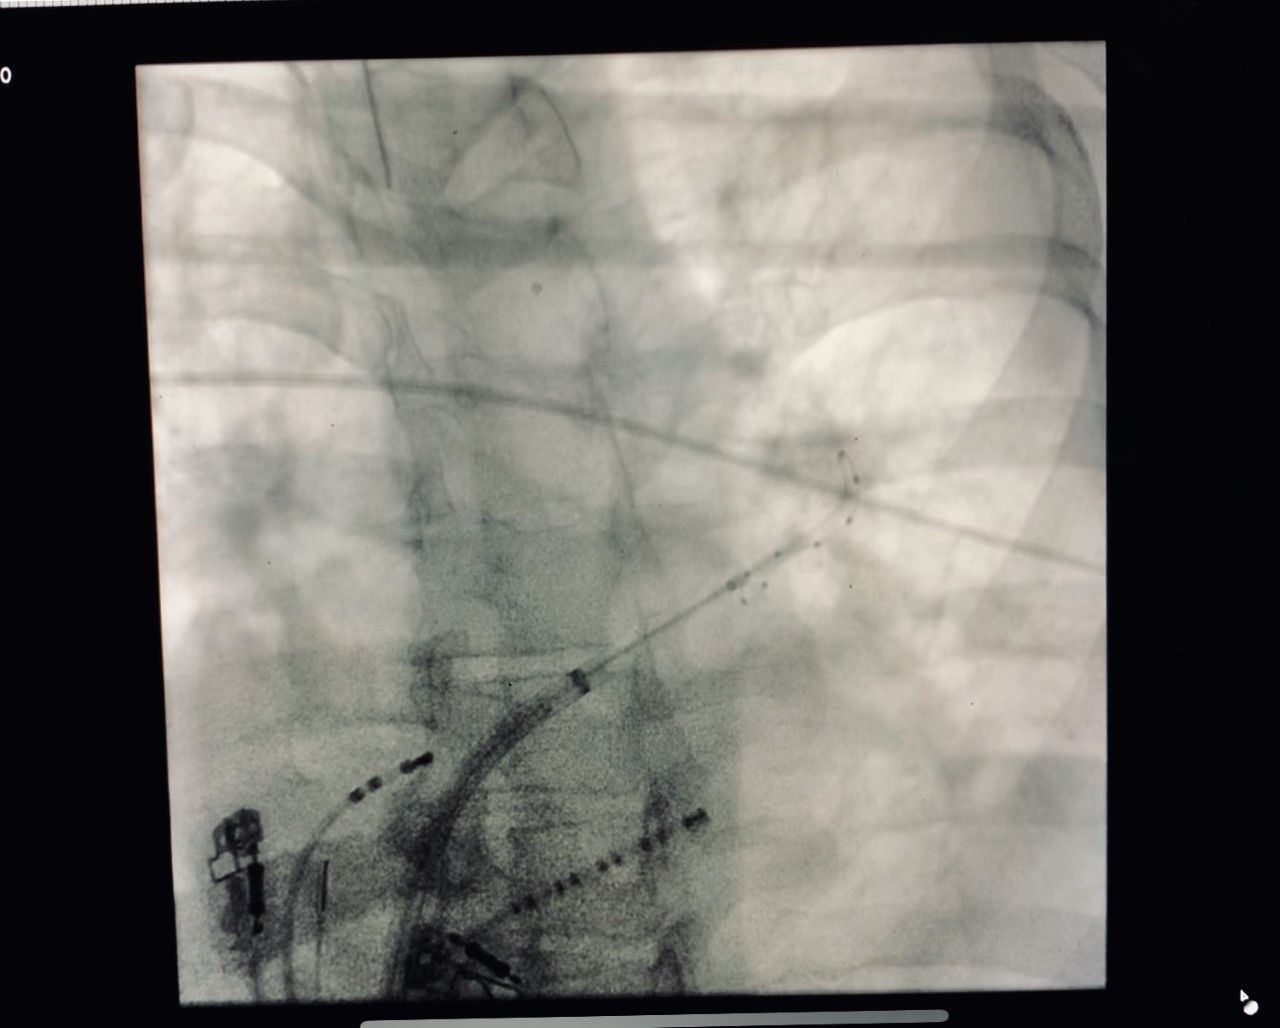

Realicé mi formación como médico general en la Universidad Autónoma de Veracruz Villa Rica, posteriormente la especialidad en medicina interna durante dos años en centro medico nacional Adolfo Ruiz Cortinez UMAE 14 en Veracruz, recibiendo en el primer año el reconocimiento por excelencia académica y en el segundo año reconocimiento al mejor promedio de mi generación. Realicé la subespecialidad en Cardiología clínica en el Centro Médico Nacional “La Raza”, en la Ciudad de México siendo jefe de residentes en el último año de la residencia médica, durante el tiempo la sede recibió el premio a la mejor cede de formadores de cardiología 2012-2013 premio otorgado por Dr. Enrique Graube (en ese entonces Director de medicina UNAM). Entre mis actividades asistenciales y conferencias, he presentado trabajos libres a nivel internacional (congreso de falla cardiaca lisboa 2013, Congreso mundial de cardiologia 2016, 2018 en AHA) ganador del premio internacional “la imagen más bella en cardiología, sociedad europea cardiologia España 2013”, así mismo presentación de más de 35 articulos publicados en revistas indexadas, soy miembro de la sociedad mexicana de cardiología no. 2076, asociación mexicana de cardiología, Fellow in training de la American collegue of cardiology capítulo México. Miembro de la sociedad europea de cardiología ESC ID 509395. Médico adscrito en el centro médico nacional la Raza, fui profesor adjunto del curso de cardiología en el mismo centro y sindal en el exámen de certificación de cardiología clínica de la sociedad mexicana de cardiología. Desde el 2016-2018 realicé curso de alta especialidad en electrofisiología cardiaca y estimulación cardiaca , realizando cursos fuera del país para especialización en técnicas avanzadas de ablación de arritmias, actualmente me encuentro realizando en el segundo año de la maestría en Dirección y Gestión de Instituciones de salud y Especialidad en Gestión de la Salud y Bienestar Corporativo

• Arritmias